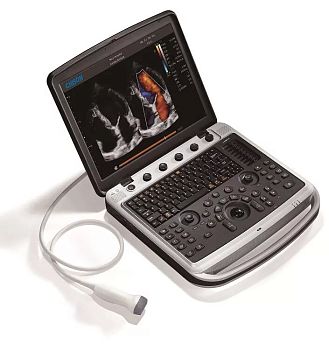

Клинические изображения

Программные опции

- VS Flow - обеспечивает высокое разрешение и высокую чувствительность сосудов/капилляров

- Эластография - опция оценки эластичности ткани с программой анализа (компрессионный метод)

- 4D Pro программное обеспечение (n-Slice, Any-Cut, Q-cut)

- CW - постоянно-волновой доплер

- TDI - тканевый доплер

- Цветной М-режим

Доступные датчики

- Мультичастотные конвексные датчики

- Мультичастотные линейные датчики

- Секторные фазированные датчики

- Широкополосные микроконвексные датчики

- Специализированные конвексные датчики для объемного сканирования в реальном времени

- Специализированный микроконвексный внутриполостной датчик для объемного сканирования в реальном времени

- Широкополосный внутриполостной датчик

- Эндоректальный ректальный датчик

- Эндоректальный биплановый датчик